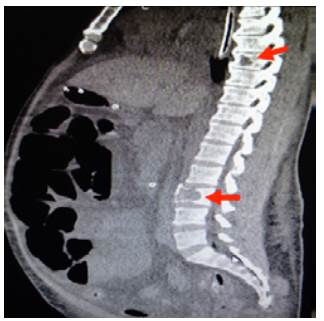

On admission, myopathy studies were initiated (Table 1) and muscle enzymes, electromyography and muscle biopsy were requested, which excluded inflammatory myopathy. The autoimmune profile and HIV were negative. Adult Pompe disease was considered, but acid maltase was normal and syringomyelia was ruled out using contrast-enhanced cervical and brain MRI (Figure 3). Considering the lytic lesions observed in chest tomography, neoplasms (myopathy as a paraneoplastic phenomenon) were looked for as there was no compromise of the pulmonary parenchyma, only bibasal subsegmental atelectasis. No masses or organomegaly were observed in abdomen images (Figure 4).